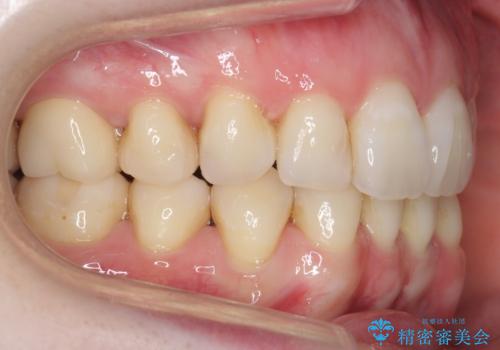

八重歯の部分は抜歯し、奥に入っていた前歯を前に移動させました。

矯正治療後にしっかり全体の虫歯治療も行い、とても良い状態にできたと思います。

犬歯を抜いたとしても、矯正治療を短期間で終わらせて歯に負担がかからないようにし、虫歯治療その分しっかり行うのもメリットがあるのではないかと思います。